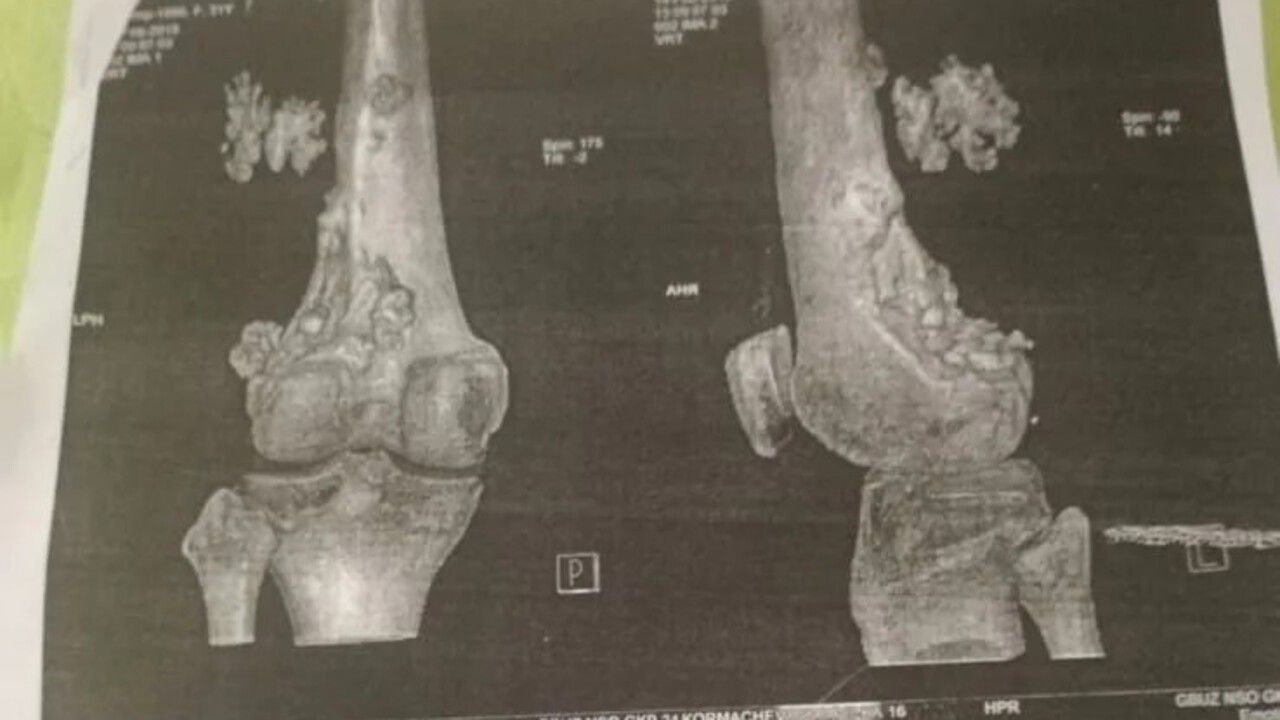

39-летняя Дарья Кормачева с 2009 года борется с остеосаркомой левого бедра. В шутку она называется себя «железной леди», так как её тело частично состоит из металла: в ноге установлен эндопротез, а в пояснице — металлоконструкция. История сибирячки — в материале Горсайта.

В итоге опухоль удаляли около 20 раз, но она постоянно рецидивировала. Точный диагноз врачи долго не могли поставить. Только в 2019 году медики подтвердили остеосаркому. Потребовалась серьёзная операция: удаление поражённой кости и установка эндопротеза. Во время процедуры хирурги также убрали образование в лёгких.